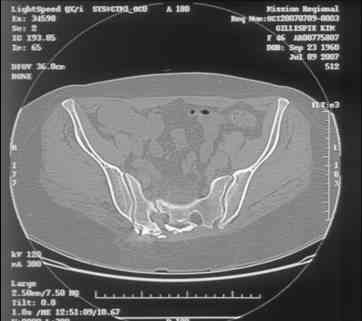

Re: Sacral Non-Union

David Zamorano 25 Август 2007, 21:05

Here is a magnified view. Sorry about the quality but the CT was scanned into our system.

dave

Отправитель: Chip Routt 25 Август 2007, 21:08

Thank you...it might help to remove the disengaged and other iliosacral screws then insert longer lag screws into the upper sacral segment and if anatomically feasible into the second sacral segment as well.

You could do it percutaneously and even add an electrical stimulation device if that seems reasonable.

At this point, I'd ignore the right pubic root issue if asymptomatic.

If simple measures such as those above fail, then you could remove it all, take down the sacral fracture site, refix with alternate techniques, and bone graft.

Chip